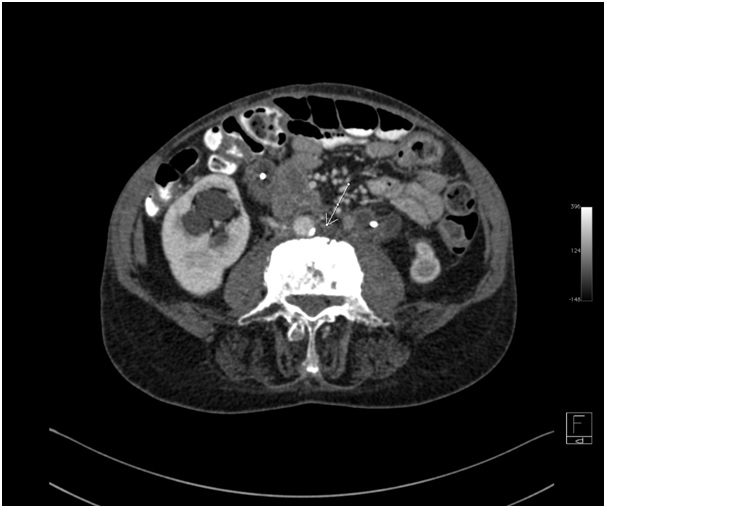

Idiopathic retroperitoneal fibrosis, or Ormond’s disease, is a rare syndrome which is in essence the deposition of pathological fibrous tissue in the retroperitoneal space. In most cases, it is initially asymptomatic, but as the disease progresses, clinical symptoms develop. The main complaint are abdominal pain and symptoms resulting from the involvement of ureters, arterial and venous vessels. Diagnosis is based on computed tomography or magnetic resonance imaging, demonstrating a fibrotic tissue mass accumulated in the retroperitoneal space. Due to the typically late presentation of clinical symptoms, a diagnosis is difficult and is often made after complications occur. In our article, we present the case of a 71-year-old patient in whom coexisting ankylosing spondylitis and retroperitoneal fibrosis were diagnosed 15 years after non-specific abdominal pain occurred.